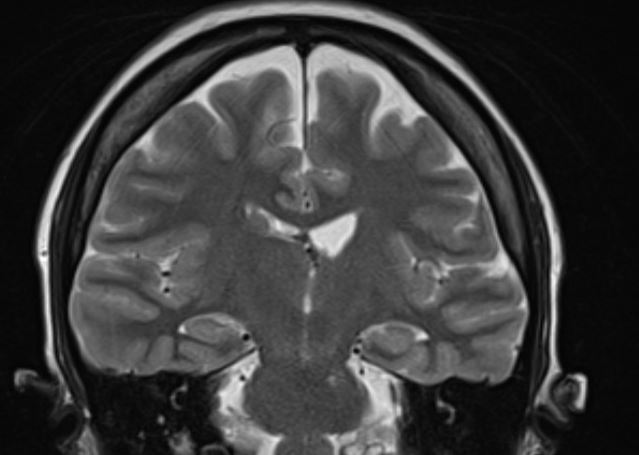

The structural correlates of the above EEG findings appear below. There is enlargement of the left-ventricular system, atrophy of the head, body and tail of the caudate nucleus and the left hemisphere appears modestly smaller in size than the right, most evident on axial sequences. The MRI was done while the patient was quite restless. As you can see from these pictures, the left occipital cortex and the left thalamus do not demonstrate any structural correlate to the asymmetry of alpha rhythms. However, we know from the EEG that the left hemisphere is markedly dysfunctional. Unsurprisingly, on functional MRI scans language is represented in the right hemisphere.